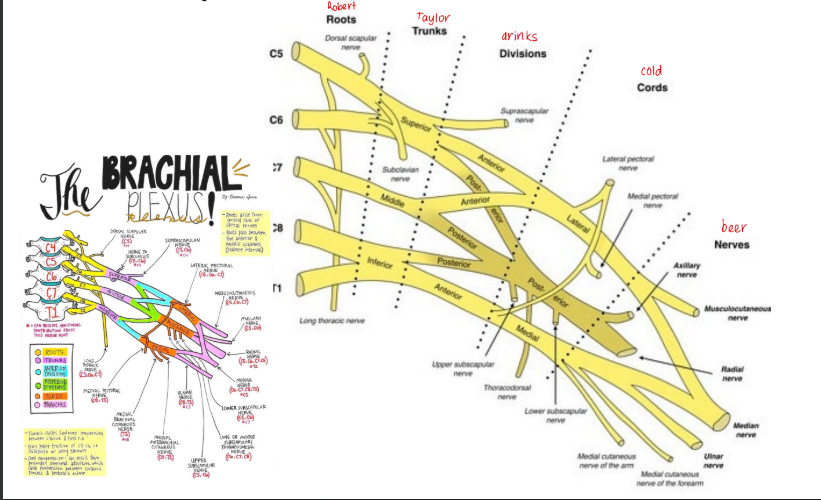

Brachial plexus

Formed from ventral rami C5 to T1

Pre-fixed, C5 large, C4 present, T1 small and T2 absent

Post-fixed, T1 large, T2 present, C5 small and C4 absent

Branches from cord

Lateral cord

Lateral pectoral nerve

Lateral root of median nerve

Musculocutaneous nerve

Medial cord

Medial root of median nerve

Medial cutaneous nerve of arm

Medial cutaneous nerve of forearm

Medial pectoral nerve

Ulna nerve

Posterior cord

Upper subscapular

Lower subscapular

Thoracodorsal nerve

Radial nerve

Axillary nerve

Erb’s point

Consists of C5, C6 ventral and dorsal division of upper trunk, suprascapular and nerve to subclavius